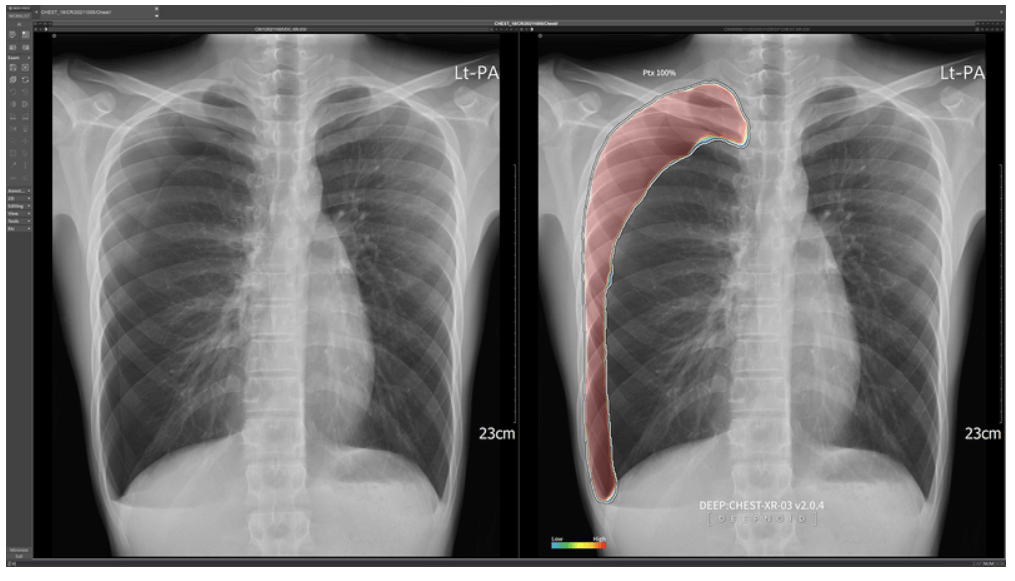

이 기업은 AI 기술을 이용한 의료 진단과 영상판독을 통해 질병을 조기 진단 할 수 있는 솔루션을 제공하는 업체입니다.

X-ray, MRI, CT 등의 영상 촬영이 많아지면서 의료진이 검토해야 할 영상물은 많아지고 있습니다. 하지만 의료인의 인력은 부족합니다. 이러한 상황에서 AI 플랫폼을 활용한 영상 진단 기술은 유용한 도구가 되고 있습니다.

자사의 DEEP AI, DEEP-PHI, DEEP-PACS와 같은 기술을 통해 영상정보를 판독하고 질병을 조기 진단합니다. 또한 임상과정에서도 사용됩니다. 이 기술의 사용 기관을 넓혀 나가고 있습니다. 사용 기관이 늘어날수록 기업에 실적이 올라갑니다.